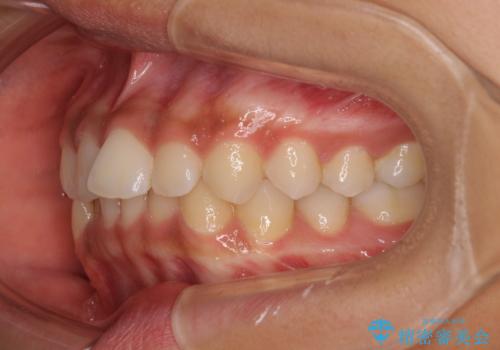

前歯のデコボコを治したい インビザライン・モデレートによる矯正治療

- 8ヶ月

- 5-10回

- 上下前歯の叢生を気にして来院された患者様です。

インビザラインでの治療を希望されていて、デコボコの程度が中等度であり、安価なパッケージにて対応可能と判断されたため、インビザライン・モデレートを用いて矯正治療を行うこととしました。